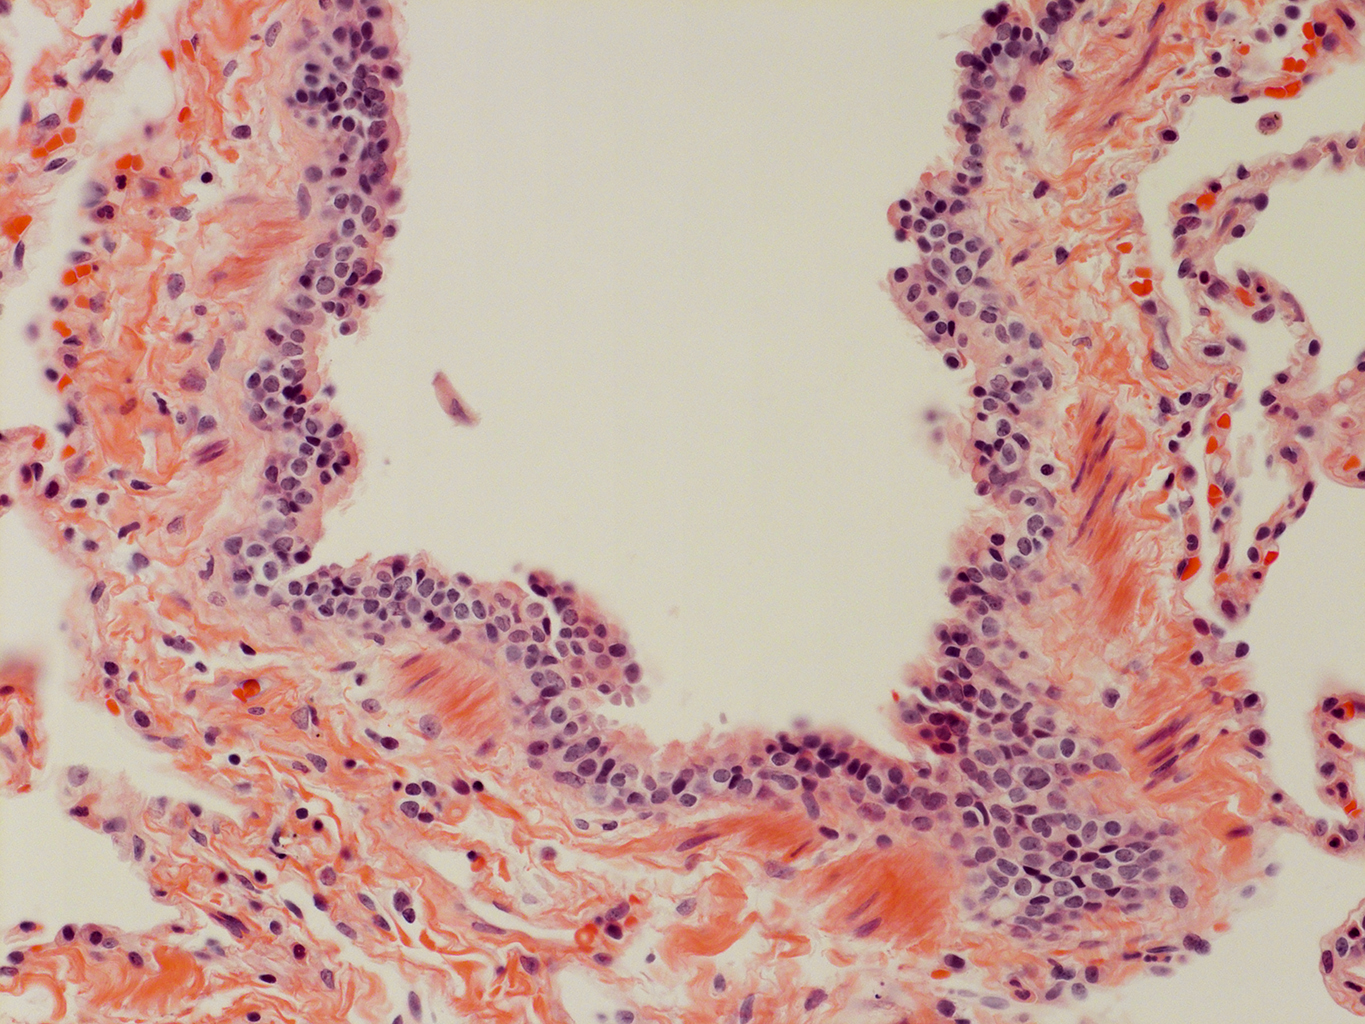

Donor tissue kindly provided by Dr. Scott Randell, University of North Carolina

Tissue Used:

LMHA-15-UNC-2017-12-19_D0037L.05HP_3_48

Gender: Male

Age:Â 43 Year Old

Race: Hispanic

Non-Smoker